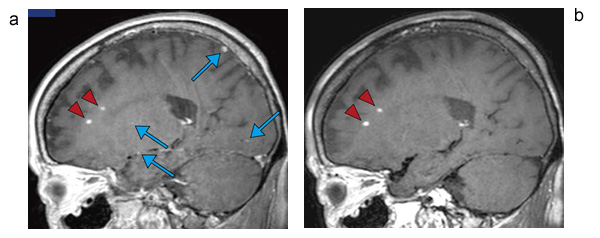

図5に,MSDE法とiMSDE法で撮像した頭部画像の比較を示す。MSDE法で目立っている頭頂部位の信号低下が,iMSDE法で改善していることがわかる。また,iMSDE法を用いた応用例を図6に示す。これは脳転移を確認するための検査で,造影後に撮像されている。図6 aは,3D-TSE法で撮像したT1強調像である。病変部位(▲)と血液信号(↑)が,ともに高信号として描出されており,病変部位の見極めを困難にする可能性がある。図6 bは,3D-MSDE-TSEで撮像した画像である。血液信号の抑制によって,病変部位のみを高信号として描出するため,検出能力の向上が期待できる。

図6 iMSDE法を用いた造影後の脳転移検査

a:3D-TSE法で撮像したT1強調像。病変部位(▲)と血液信号(↑)がともに高信号として描出されており,病変部位の見極めを困難にする可能性がある。

b:3D-MSDE-TSEで撮像した画像。血液信号の抑制によって,病変部位のみを高信号として描出するため,検出能の向上が期待できる。

(画像ご提供:東北大学様)